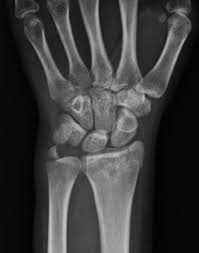

Anatomía de la articulación radiocarpiana

La articulación radiocarpiana se configura como una articulación sinovial de tipo elipsoide, siendo su función cardinal la unión entre la epífisis inferior del radio y el carpo. La denominación "radiocarpiana"…